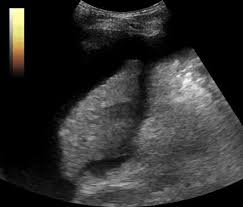

복부 초음파는 비침습적이며 방사선 노출이 없는 안전한 검사 방법으로, 초음파(ultrasound)를 통해 복부 내 장기들의 상태를 실시간으로 확인할 수 있는 진단 도구입니다. 복부 초음파로 알 수 있는 것 중에서는 특히 간, 담낭, 췌장, 비장, 신장, 방광, 대동맥, 소장, 대장 등의 상태를 파악할 수 있으며, 질환의 조기 발견에 탁월한 효과를 보입니다.

간 관련 질환

- 지방간: 간 조직 내 지방 축적 상태 확인 가능

- 간경화: 간 표면의 거칠음, 크기 변화, 비장 비대 여부 등 확인

- 간암, 간종양: 실질 내부에 덩어리 유무 탐색